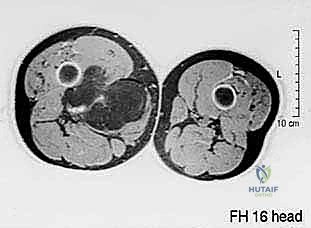

التشريح المعقد للفخذ: ساحة المعركة الجراحية

لفهم مدى تعقيد جراحة استئصال أورام الفخذ، يجب أن نلقي نظرة على التشريح الدقيق لهذه المنطقة. ينقسم الفخذ إلى ثلاث حجرات رئيسية (Compartments)، وكل حجرة تحتوي على عضلات، أوعية دموية، وأعصاب حيوية:

- الحجرة الأمامية (Anterior Compartment): تحتوي على العضلة الرباعية (Quadriceps) المسؤولة عن تمديد الركبة، بالإضافة إلى العصب الفخذي.

- الحجرة الخلفية (Posterior Compartment): تحتوي على عضلات المأبض (Hamstrings) المسؤولة عن ثني الركبة، ويمر من خلالها العصب الوركي (Sciatic Nerve) الأهم والأكبر في الجسم.

- الحجرة الإنسية أو الداخلية (Medial Compartment): تحتوي على العضلات المقربة (Adductor Muscles)، وهي منطقة شديدة الحساسية لمرور الشريان والوريد الفخذي (Femoral Vessels) والعصب السدادي.

عندما تنشأ الساركوما في أي من هذه الحجرات، فإنها تدفع الأنسجة الطبيعية وتلتصق بالأوعية والأعصاب. براعة الأستاذ الدكتور محمد هطيف تتجلى في قدرته على فصل هذه الأورام واستئصالها مع "هامش أمان" (أنسجة سليمة تحيط بالورم) لضمان عدم ترك أي خلايا سرطانية، مع الإبقاء على الهياكل الحيوية التي تضمن للمريض القدرة على المشي لاحقاً.